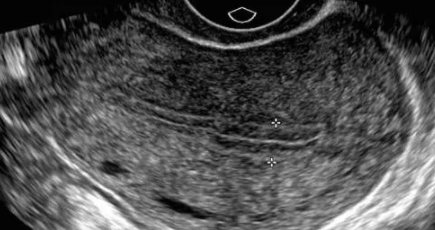

子宮內(nèi)膜厚度在月經(jīng)的不同時間段厚度會不同,月經(jīng)干凈以后卵泡期測量內(nèi)膜厚度通常在5-7mm,而在排卵后黃體期甚至可以達(dá)10-16mm,如果月經(jīng)后測量內(nèi)膜偏厚可能會是子宮內(nèi)膜息肉的問題,但是若是沒有不孕沒有不規(guī)則出血,可以不做處理,觀察就好。

絕經(jīng)后子宮內(nèi)膜若是子宮內(nèi)膜超過5mm是異常,若是因乳腺癌服用他莫昔芬,不超過8mm,對于尤其合并有絕經(jīng)后出血的情況尤其要注意需要警惕子宮內(nèi)膜癌的情況。

經(jīng)陰道超聲檢查 (TVS )對篩查和診斷分流起關(guān)鍵作用, 是評估育齡婦女子宮內(nèi)膜的一線診斷工具。鹽水灌注的超聲宮腔造影術(shù) (SIS )用于評估宮腔內(nèi)膜的局部病變, 是一種安全、 經(jīng)濟(jì)高效、 易用的工具。 宮腔鏡檢查(HYS ) +定向活檢是評估子宮內(nèi)膜的 “金標(biāo)準(zhǔn)” 。 目前尚無證據(jù)表明, 任何使用流體的宮內(nèi)診斷過程可能使子宮內(nèi)膜癌細(xì)胞進(jìn)入腹膜,導(dǎo)致疾病惡化或預(yù)后不佳。另外還有診斷性刮宮術(shù)、Pipelle 子宮內(nèi)膜取樣器,Pipelle 子宮內(nèi)膜取樣器是不需要麻醉的子宮內(nèi)膜的真空取樣, 其診斷的準(zhǔn)確率與診斷性刮宮基本一致, 是在當(dāng)前實(shí)踐中最微創(chuàng)的方法。